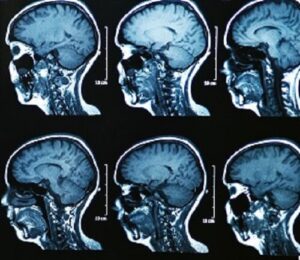

- визуальных исследований (рентгенографии, компьютерной томографии, магнитно-резонансной томографии) для установления особенностей новообразования, диагностики наличия отдаленных метастазов;